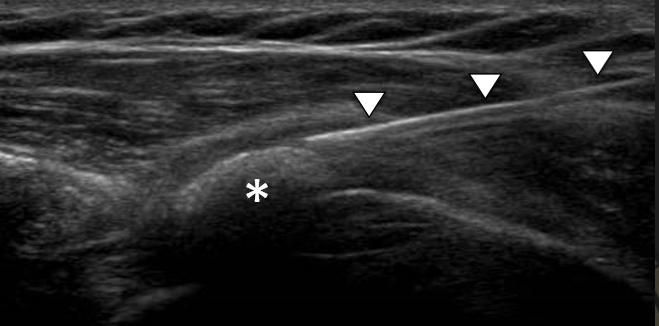

Poleg kliničnega pregleda je potrebna RTG diagnostika in UZ preiskava ramena, v določenih primerih tudi preiskava z magnetno resonanco. Običajno se vnetje zdravi s počitkom, analgetično terapijo, fizikalno terapijo. V določenih primerih svetujemo tudi terapijo z udarnimi valovi (ESWT).

V kolikor so kalcinati večji od 8mm in so enakomerne strukture lahko pod ultrazvočno kontrolo opravimo tudi punkcijo kalcinata in kalcinat izperemo. Poseg se opravi v lokalni anesteziji in traja približno 30 minut. Bolečina lahko traja tudi nekaj dni po posegu. V teh primerih svetujemo jemanje analgetikov. Nekaj dni po posegu priporočamo postopno stopnjevanje aktivnosti, izvajanje vaj, plavanja, nordijske hoje in fizikalne terapije in po 2 -3 mesecih vrnitev željenim aktivnostim.